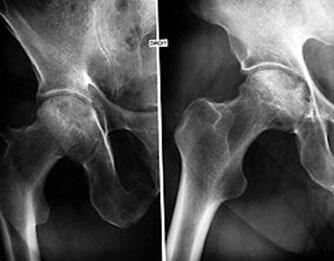

| L'ostéoarthrite, ou arthrose, est l'une des formes d'arthrite les plus courantes, une affection chronique dégénérative qui touche les articulations, responsable de douleurs et de multiples désagréments entravant la mobilité. Un certain nombre de suppléments nutritionnels comme la SAMe, le sulfate de chondroïtine ou de glucosamine ou des extraits de plantes aident non seulement à soulager la douleur mais, pour certains d'entre eux, également à reconstruire les articulations. |

L'objectif du traitement de l'arthrose est, avant tout, de soulager la douleur et la raideur articulaires tout en freinant ou stoppant le développement des lésions du cartilage. La médecine conventionnelle traite principalement l'arthrose avec des analgésiques, des anti-inflammatoires non stéroïdiens ou stéroïdiens qui, pratiquement tous, outre le fait qu'ils ont de nombreux effets secondaires, contribuent par un mécanisme ou par un autre à dégrader l'articulation. |

La détérioration des articulations, principalement celles du genou, est plus lente chez des personnes atteintes d'arthrose mangeant des quantités importantes d'aliments riches en antioxydants que chez celles qui en consommaient peu (McAlindon T.E. et al., 1996). Des études ont ainsi montré que les vitamines C et E exerçaient un effet bénéfique dans le traitement de l'arthrose. Une consommation déficiente en vitamine C, ce que l'on rencontre fréquemment chez des personnes âgées, perturbe la synthèse du collagène, une protéine particulièrement importante pour les cartilages (Bates, 1977). |